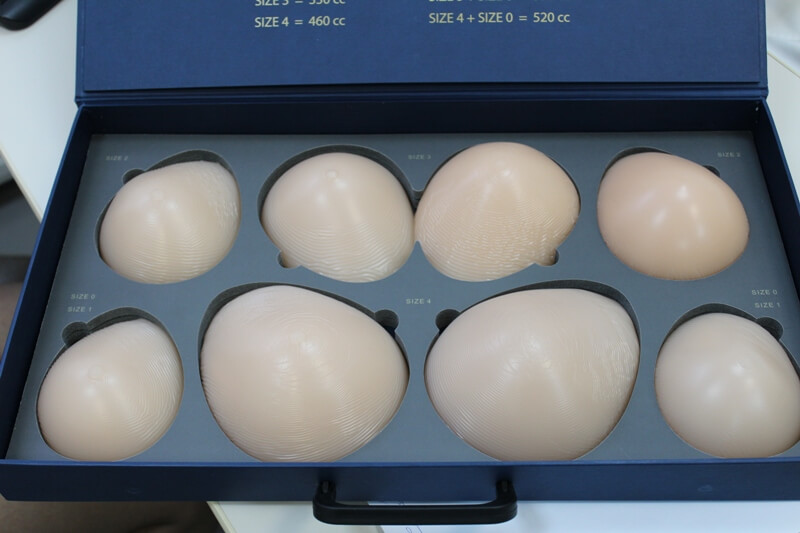

Анатомические импланты Eurosilicone

Раздел: Визуальный дайджест